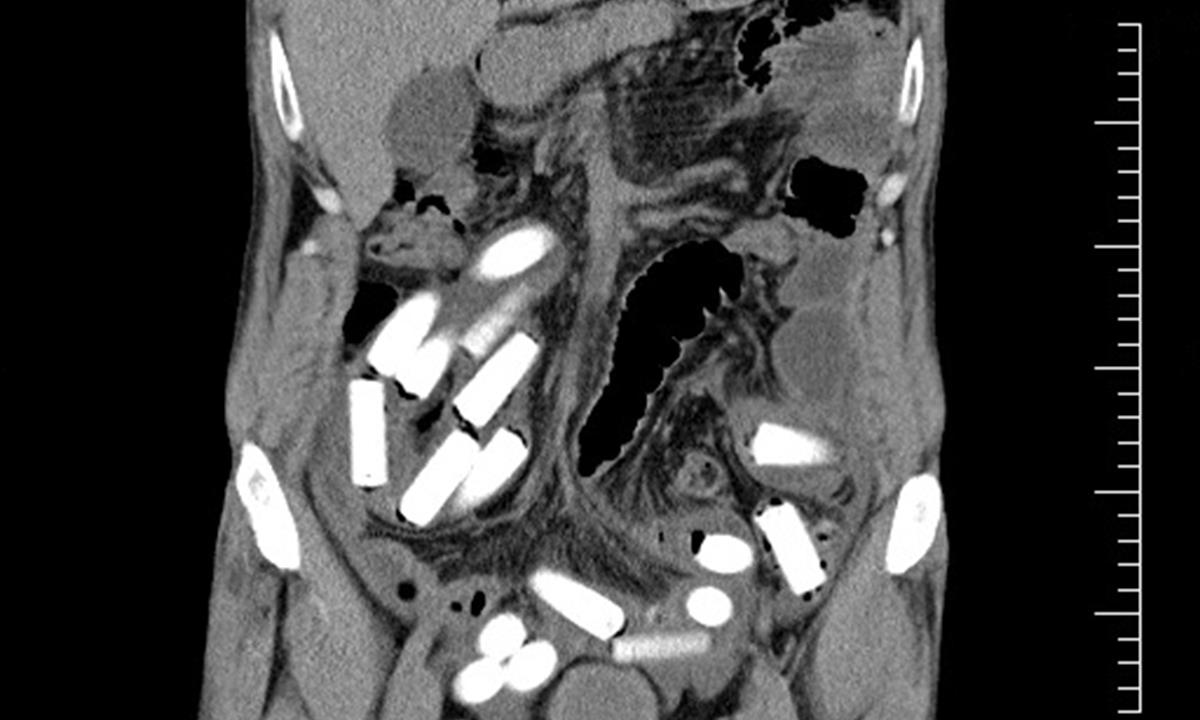

Dnes vyloučil rumunský pašerák ze svého těla poslední z 55 kapslí s šesti sty gramy kokainu. Dalších 40 kapslí se čtyřmi sty gramy kokainu měl ukryto ve speciálním pásu na těle. Pašeráka odhalili celníci na letišti Praha Ruzyně při kontrole cestujících linky Curych – Praha.

Do Curychu přicestoval 49-letý muž z brazilského Sao Paula. Droga s největší pravděpodobností nebyla určena na český trh, kde by za ni mohl utržit až dva miliony. Cizinec je nyní ve vazbě. Za pašování drog mu hrozí dvanáctiletý trest odnětí svobody.

Jedná se o první případ „polykače“ v roce 2011, celníci na Ruzyni doposud odhalili čtyři případy pašování kokainu (cca sedm kilogramů), který byl pašován v zavazadlech, oblečení či v tělesném otvoru.